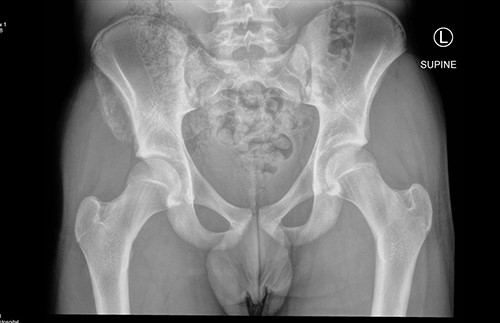

The anterior–posterior plain film X-Ray of pelvis demonstrated an avulsion fracture of the right ASIS and IC apophysis with 1.5 cm displacement (Fig. 1). Lateral view of the hip showed no extension into the joint. There was no radiological evidence of chronic overuse or previous injury. Computed tomography (CT) imaging was performed to better identify the injury; 3D volume reconstruction clearly demonstrated the unique fracture pattern of an ASIS avulsion in addition to an avulsion of the distal iliac apophysis extending ~5 cm with the described displacement (Figs 2–4).

3D reconstruction of tomographic CT scan illustrating avulsion fracture of ASIS and IC apophysis with its latero-inferior displacement (P - Posterior).